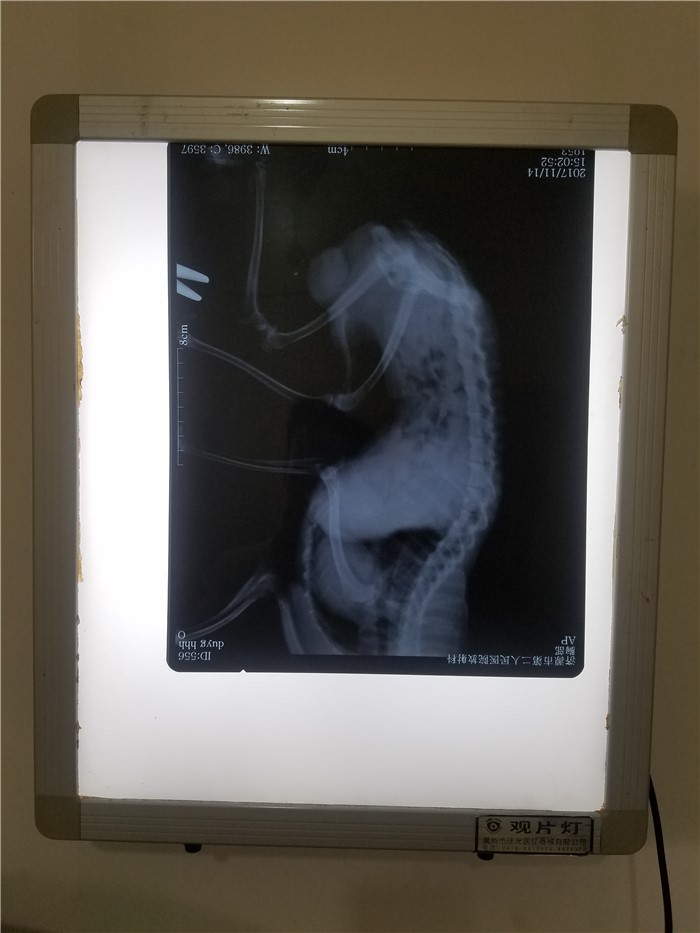

观片机